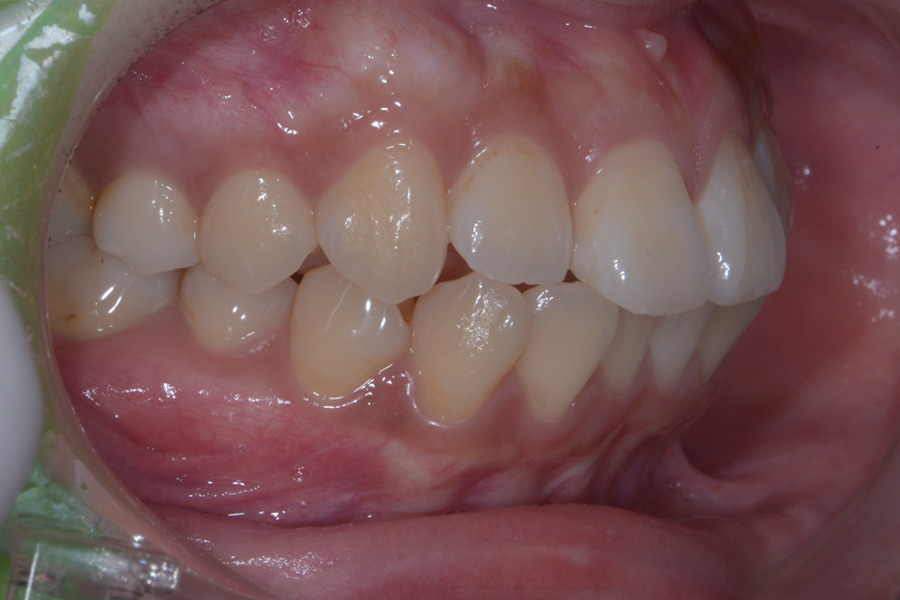

【20代女性】

飛び出ている2本の歯を引っ込めて

下の捻じれている歯を並べたい

治療後

主訴 飛び出ている2本の歯を引っ込めて下の捻じれている歯を並べたい

治療内容 ハーフリンガル矯正(上顎裏側・下顎表側矯正)